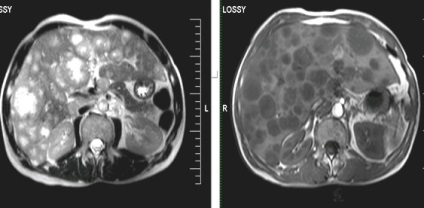

Több májáttétek.

Egyedi kis májáttétek; hasonlóság a natív vizsgálat hemangiomas.

Ugyanez a beteg. Postkontrastnye tomográfia. Egyedi kis májmetasztázisok ellentétben hemangiomas tomogramjait a korai és a késői fázisban válik parenchymás hypointense a natív vizsgálat (gyors enyhülést kontraszt kritérium 1 perc).

Áttétek a májban, a jobb vesét.